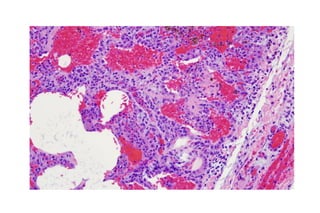

Desquamative Interstitial Pneumonia

(DIP)

• Benign form of adult ILD

• Linked to smoking

• Very responsive to steroids

• Most cases of pediatric DIP

are related to inborn errors

of surfactant metabolism